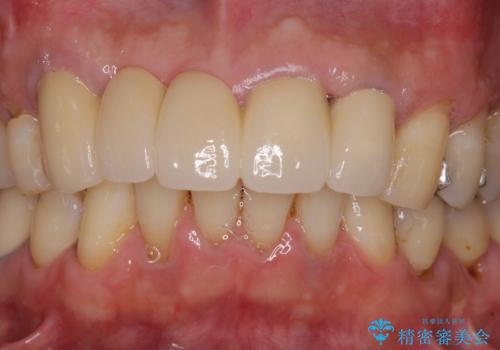

露出していた歯根や金属の縁が見えてしまい、人前で話すときの目線が気になっていらっしゃいましたが、歯肉の位置に縁を合わせてことで自然な仕上がりとなりました。

露出していた歯根が覆われるため、歯冠が長く見えてしまうことが懸念されましたが特に気になることはなく、患者様には大変満足していただきました。